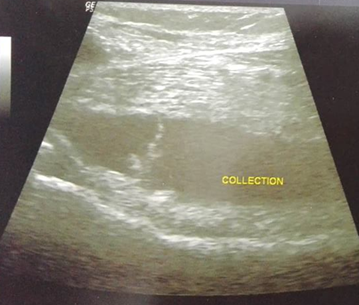

Doppler ultrasound showed no thrombophlebitis but objectified a right popliteal cyst ruptured in the calf (Figure 1 & 2) with a huge fluid collection into the right gastrocnemius muscle layers (Figure 3). The patient was treated with oral and topical nonsteroidal anti-inflammatory drugs for two weeks with favorable outcomes: progressive disappearance of pain and swelling of the calf with return to normal ten days after treatment. The two-week follow-up ultrasound showed complete resorption of the fluid collection in the calf.

Figure 1 Right calf ultrasound: Popliteal cyst.